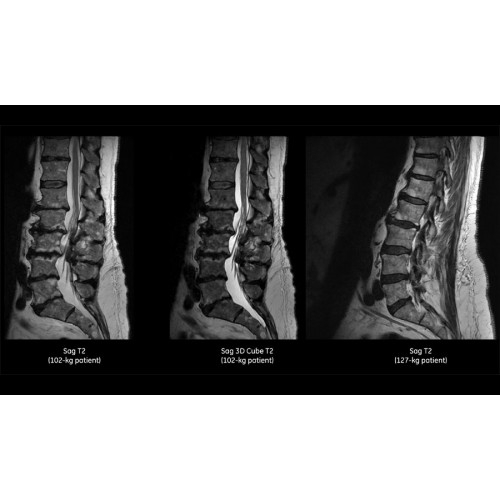

• Технология Digital Surround Technology (DST) — это новая технология объемной оцифровки данных, объединяющая сигналы от каждого элемента катушки. Прекрасное соотношение сигнал/шум и чувствительность поверхностных катушек в сочетании с превосходной однородностью и высокой проникающей способностью встроенной радиочастотной катушки — все это позволяет создавать качественные изображения не только позвоночника, но и всего тела.

Помимо технологии 97 РЧ-каналов, SIGNA Pioneer использует магнит 3.0Т высокой однородности, предназначенный для повышения качества визуализации во всех областях, а также закладывающий прочный фундамент для долгосрочных инвестиций и роста клинических возможностей.